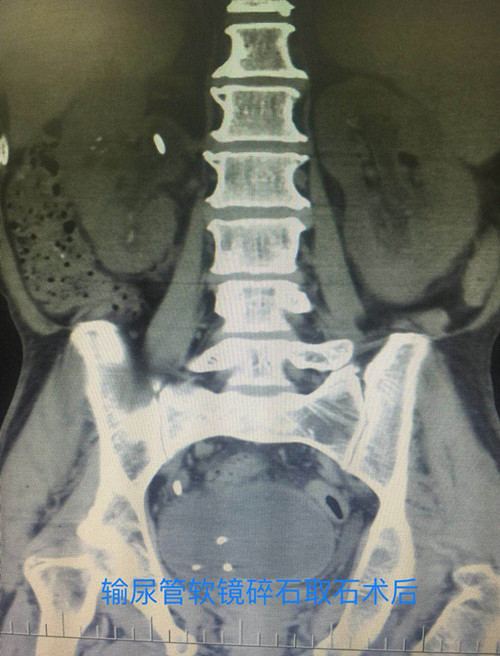

泌尿外科手术效果图